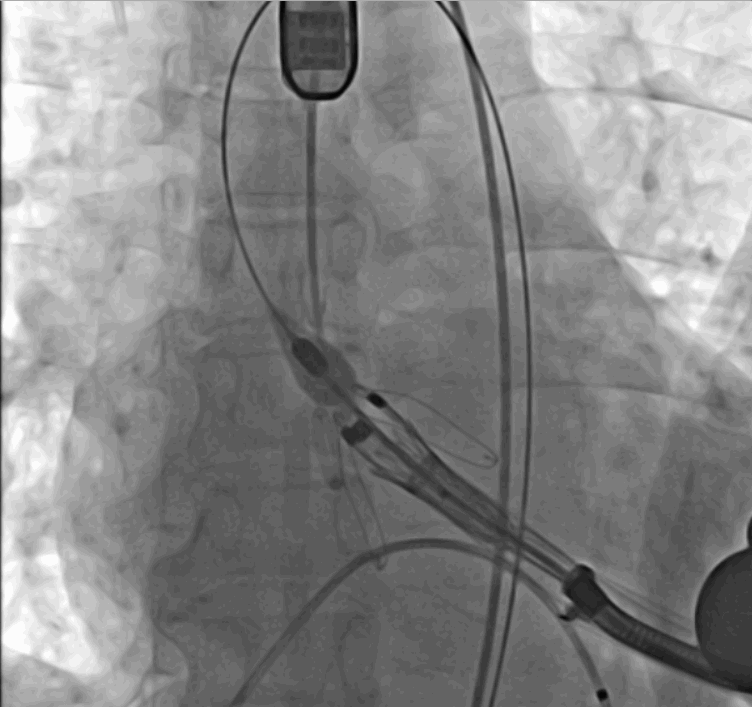

手術(shù)采用經(jīng)心尖入路,對患者進(jìn)行全麻后,在左側(cè)心尖處做3-4cm微創(chuàng)手術(shù)切口,在DSA及超聲引導(dǎo)下手術(shù)順利完成。從導(dǎo)入器械到完成瓣膜置入,僅耗時約10分鐘。術(shù)后即刻主動脈瓣返流程度由術(shù)前大量返流轉(zhuǎn)為消失,患者于導(dǎo)管室拔除氣管插管,次日由ICU轉(zhuǎn)入普通病房。

術(shù)中瓣膜釋放過程